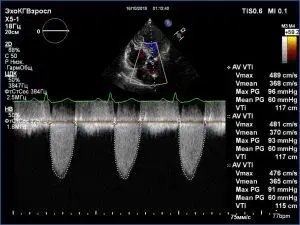

Perform evaluation of rheumatic valvular lesions with echocardiography.